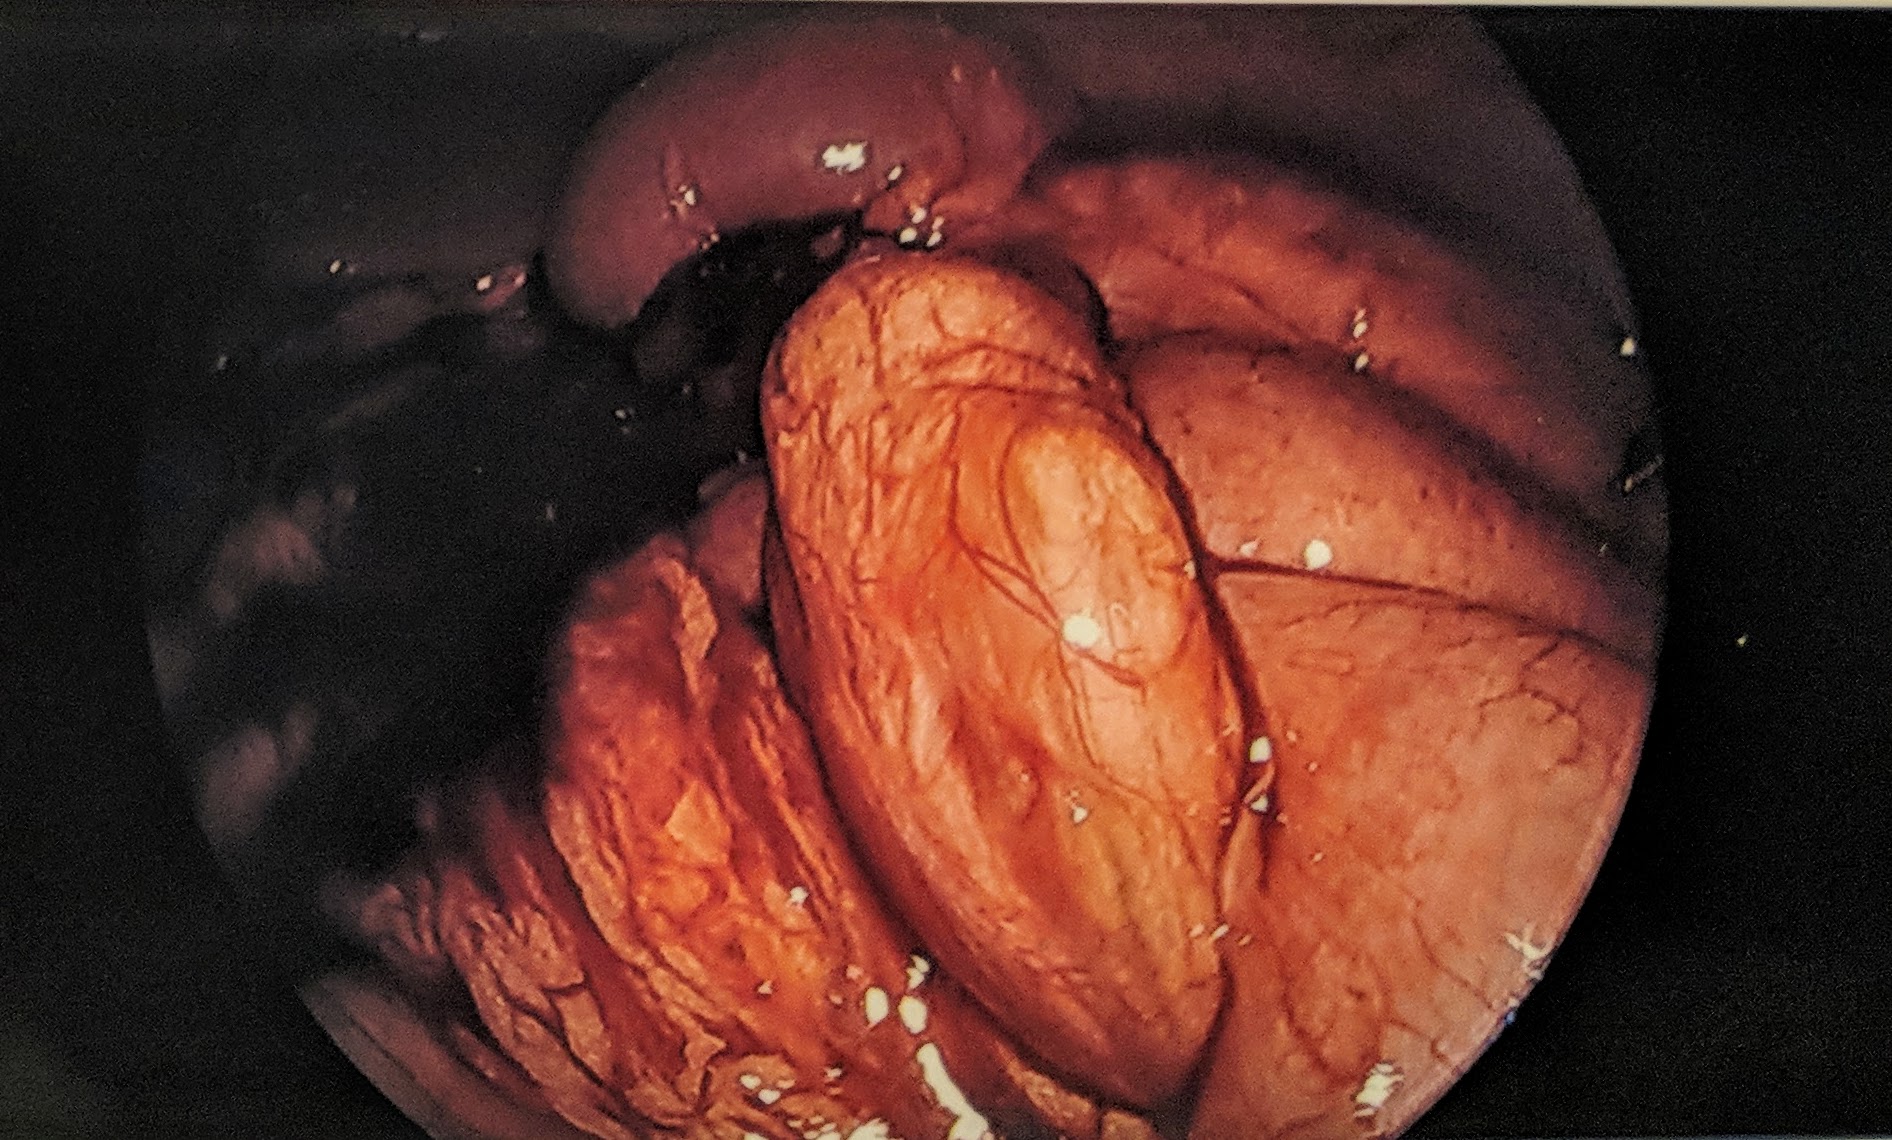

The omentum is a fascinating apron of fat within the abdomen which not only keeps our organs in place but also plays an immunological role. The omentum’s central role is the abdominal defenseman, it adheres to sites of inflammation and provides leukocytes to combat infection. In Theo’s case the omentum had adhered to the sites of his previous bowel surgeries, stretching across a portion of his small intestine. This part of the small bowel proceded to push through the stretched omentum- creating a donut-like shape- and then curved back around and came back through the same hole.

This kink in the intestine had been developing since Theo’s first symptoms in February. During the procedure, the team trimmed back the omentum, releasing Theo’s small intestine. They then inspected most of small intestine to examine other sites of adhesion but felt no further alterations were necessary. We found this pathophysiology to be fascinating, as did Theo. He even got surgical pictures as a keepsake. He enjoys retelling the story to his sisters with these graphic images.